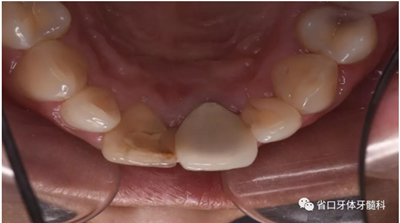

口腔檢查:口腔衛(wèi)生狀況一般,11牙冠變色,近中鄰面見(jiàn)齒色填充物,舌側(cè)窩內(nèi)見(jiàn)白色充填物,邊緣見(jiàn)黑色齲壞物,近中探及懸突,叩痛(土),松(—),冷診無(wú)反應(yīng);21烤瓷全冠修復(fù),烤瓷冠顏色未知,唇側(cè)齦緣發(fā)黑,叩痛(土),松(—)。圖1/2

圖1 治療前患牙唇側(cè)觀

圖2 治療前患牙舌側(cè)觀